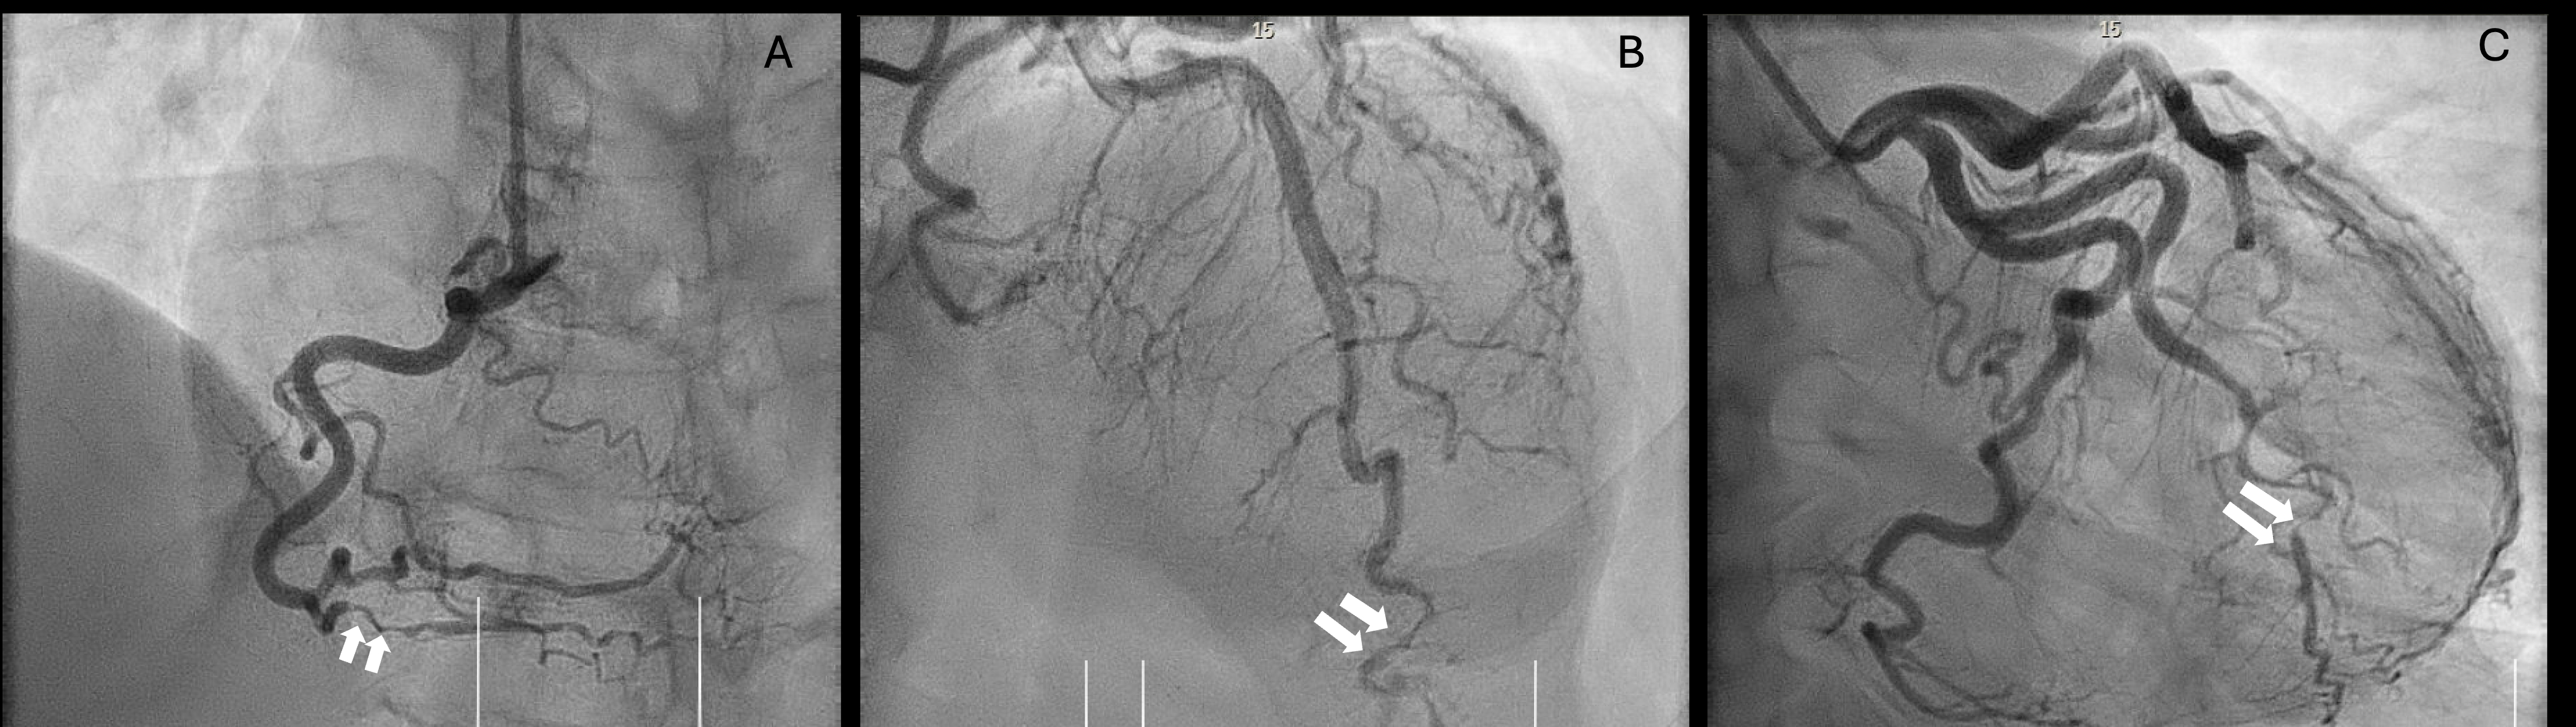

A 58-year-old woman with past medical history of hypertension and depression presented to an emergency room (ER) with acute chest pain after intense running and was diagnosed with single vessel SCAD of the right coronary artery on coronary angiography. She was treated with dual antiplatelet therapy (DAPT) for 30 days and beta blockers without recurrent angina. One year later, she began taking a GLP-1RA (semaglutide 0.25 mg SQ once weekly) for weight loss, and developed extreme nausea and vomiting hours after her first dose. While retching, she experienced chest pain reminiscent of her prior SCAD episode and presented to the ER. Serial ECGs showed dynamic inferolateral ST depressions. Her initial high-sensitivity troponin I was 224 pg/mL and peaked at 15,492 pg/mL. Transthoracic echocardiogram showed normal function and no wall motion abnormalities. Coronary angiography revealed triple-vessel Type 2 SCAD involving the first obtuse marginal branch, distal left anterior descending artery, and posterior descending artery; each with TIMI 3 flow and not requiring percutaneous coronary intervention. Her chest pain was controlled with oral nitrates and beta blockers. She was prescribed DAPT with aspirin and clopidogrel for 6 months and discharged home with recommendation for outpatient fibromuscular dysplasia screening and cardiac rehabilitation. She was cautioned to discuss with her outpatient providers prior to reinitiation of GLP-1RAs.